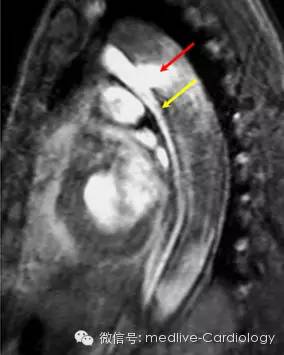

核磁共振成像(MRI)则是另一项断层成像检查,同样有超过90%的敏感度和特异度。MRI可以准确识别内膜撕裂部位、夹层扩展范围以及主动脉功能不全的情况。MRI不存在电离辐射,并且某些序列可以不使用对比造影剂。对于慢性夹层患者而言,MRI是进行一系列评估的优选手段。可惜的是,MRI在急性病例中不一定可行。

下图是心脏收缩早期的矢状位MRI梯度回波序列,可以看到血液通过内膜破口从前面较窄的真腔喷涌至后面较宽的假腔中(红色箭头)。内膜隔层显示为线状等信号影,将真腔和假腔分隔(黄色箭头)。